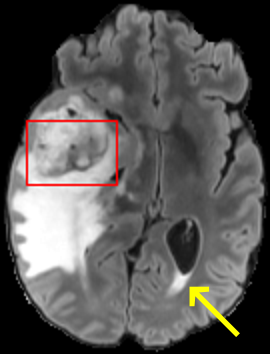

To test the impact of the iterative refinement on YODA’s translation quality, we compared regression and diffusion sampling on the RS data and present additional generation examples in Fig. 6. We observe that diffusion sampling visually resembles the appearance of the acquired images. Regression sampling preserves key anatomical features – the GM/WM boundary, WMHs (Fig. 4), the outline of the pallidum (Fig. 6) – but omits many high-frequency features. To investigate whether iterative refinement during diffusion sampling adds relevant and systematic medical information or only imitates acquisition noise, we performed ExpA sampling, i.e. averaging the output of several ( or ) diffusion trajectories. We observed a gradual loss of high-frequency details when increasing the (see also the supplementary video), indicating that the effect of the iterative refinement is non-systematic. For , the images are visually almost indistinguishable from the initial regression solution (see the supplementary video, and Fig.4 and 6). We directly compared the synthesis results of ExpA () and regression sampling quantitatively and found the differences to be minimal (SSIM: 99.73%, PSNR: 45.30 dB), i.e. diffusion sampling approaches the initial regression solution for a high . The quantitative analysis of the image quality (Tab. 1) showed that diffusion sampling impairs the assessed SSIM and PSNR in comparison to regression sampling for both the in- and external test sets, which we attribute to noise generation (Sec. 3.1). In turn, ExpA averages improved both metrics and, for , performed mostly on par with the regression solution in both test sets in terms of SSIM, while the PSNR in the RS was slightly increased (Tab. 1). However, we observed that ExpA sampling YODA improves the replication of systematic 3D low-frequency image intensity drifts (bias fields) due to the 3D synchronization in 2.5D diffusion sampling. Yet, this apparent advantage did not generalize to the external MBB dataset, as bias fields are MR protocol-specific.

To assess the suitability of YODA-generated images for WMH detection independent of segmentation tools, we also calculated the CNR (15) of WMHs. This confirmed that the contrast of WMHs is preserved in the regression images, whereas we noted slightly reduced WMH contrast for diffusion and ExpA-sampled images (Tab. 1).

On the RS data (Tab. 1), regression sampling of YODA significantly outperformed all competing methods both w.r.t. the image quality and – except the ALVR for MADM – downstream WMH segmentation, whereas the DB of Choo et al. [31] achieved an higher WMH CNR.

When analyzing the RS synthesis results (Fig. 4), we noted that most reference methods strive to imitate realistic images, but several artifacts can be observed such as hallucinated WMHs (SynDiff) and salt-and-pepper noise (SynDiff, I2I-Mamba, ResViT).